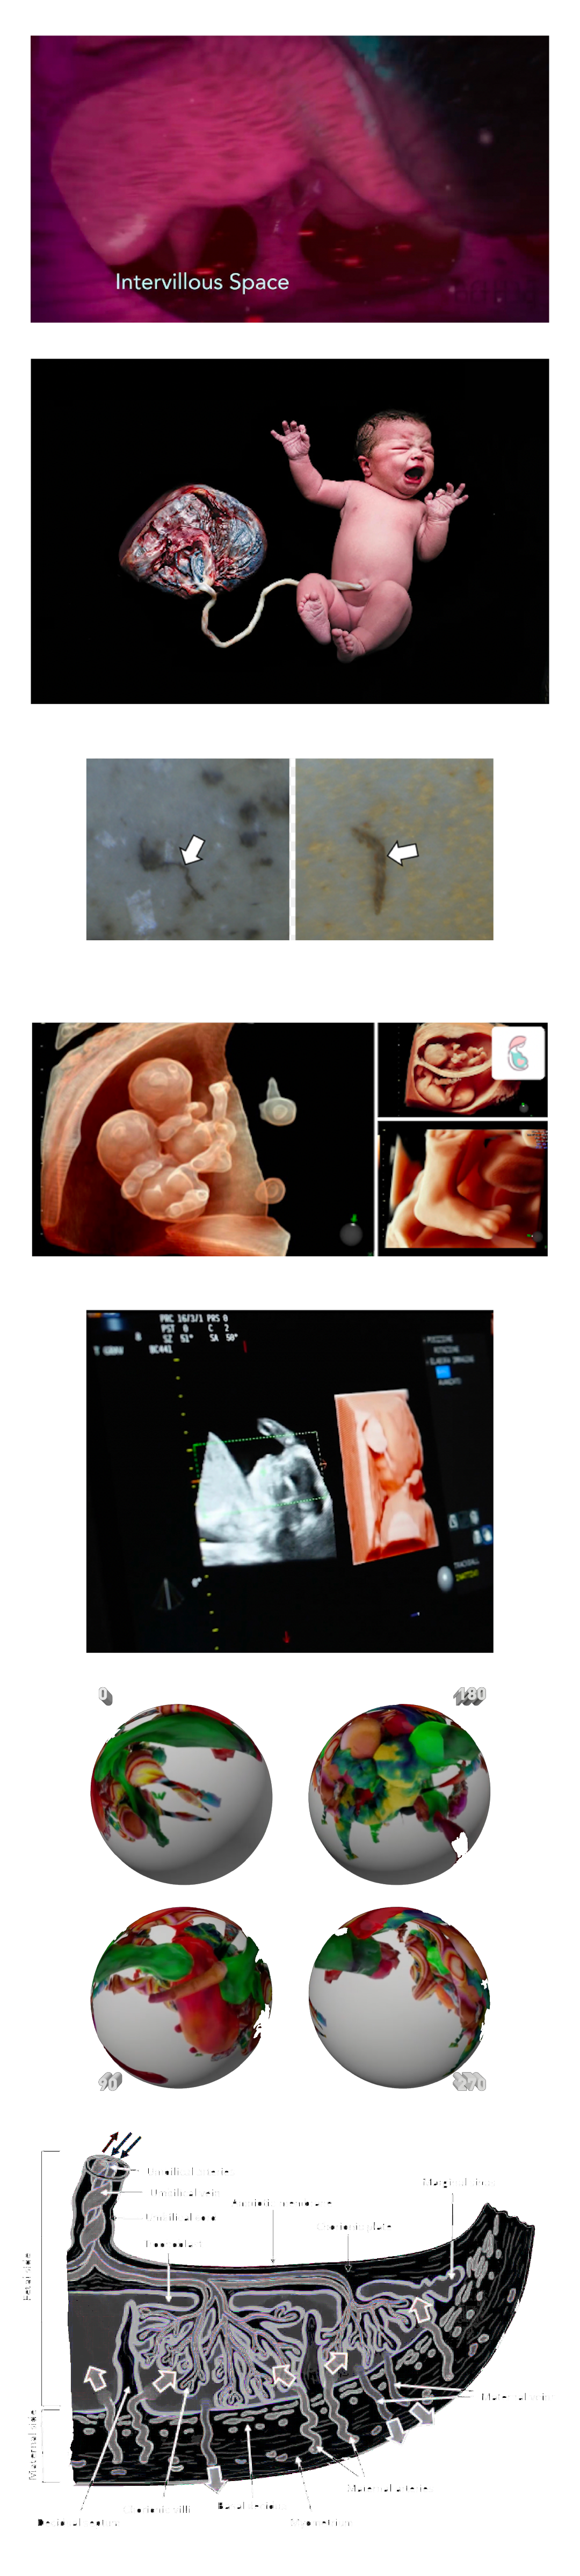

MICROPLASTICS (MPS) ARE DEFINED AS PLASTIC PARTICLES SMALLER THAN 5 MM. THEY HAVE BEEN FOUND ALMOST EVERYWHERE THEY HAVE BEEN SEARCHED FOR AND RECENT DISCOVERIES HAVE ALSO DEMONSTRATED THEIR PRESENCE IN HUMAN PLACENTA, BLOOD, MECONIUM, AND BREASTMILK, BUT THEIR LOCATION AND TOXICITY TO HUMANS HAVE NOT BEEN REPORTED TO DATE. THE AIM OF THIS STUDY WAS TWOFOLD:

1. TO LOCATE MPS WITHIN THE INTRA/EXTRACELLULAR COMPARTMENT IN HUMAN PLACENTA.

2. TO UNDERSTAND WHETHER THEIR PRESENCE AND LOCATION ARE ASSOCIATED WITH POSSIBLE STRUCTURAL CHANGES OF CELL ORGANELLES. USING VARIABLE PRESSURE SCANNING ELECTRON MICROSCOPY AND TRANSMISSION ELECTRON MICROSCOPY, MPS HAVE BEEN LOCALIZED IN TEN HUMAN PLACENTAS. IN THIS STUDY, WE DEMONSTRATED FOR THE FIRST TIME THE PRESENCE AND LOCALIZATION IN THE CELLULAR COMPARTMENT OF FRAGMENTS COMPATIBLE WITH MPS IN THE HUMAN PLACENTA AND WE HYPOTHESIZED A POSSIBLE CORRELATION BETWEEN THEIR PRESENCE AND IMPORTANT ULTRASTRUCTURAL ALTERATIONS OF SOME INTRACYTOPLASMIC ORGANELLES (MITOCHONDRIA AND ENDOPLASMIC RETICULUM). THESE ALTERATIONS HAVE NEVER BEEN REPORTED IN NORMAL HEALTHY TERM PREGNANCIES UNTIL TODAY. THEY COULD BE THE RESULT OF A PROLONGED ATTEMPT TO REMOVE AND DESTROY THE PLASTIC PARTICLES INSIDE THE PLACENTAL TISSUE. THE PRESENCE OF VIRTUALLY INDESTRUCTIBLE PARTICLES IN TERM HUMAN PLACENTA COULD CONTRIBUTE TO THE ACTIVATION OF PATHOLOGICAL TRAITS, SUCH AS OXIDATIVE STRESS, APOPTOSIS, AND INFLAMMATION, CHARACTERISTIC OF METABOLIC DISORDERS UNDERLYING OBESITY, DIABETES, AND METABOLIC SYNDROME AND PARTIALLY ACCOUNTING FOR THE RECENT EPIDEMIC OF NON-COMMUNICABLE DISEASES.

1. TO LOCATE MPS WITHIN THE INTRA/EXTRACELLULAR COMPARTMENT IN HUMAN PLACENTA.

2. TO UNDERSTAND WHETHER THEIR PRESENCE AND LOCATION ARE ASSOCIATED WITH POSSIBLE STRUCTURAL CHANGES OF CELL ORGANELLES. USING VARIABLE PRESSURE SCANNING ELECTRON MICROSCOPY AND TRANSMISSION ELECTRON MICROSCOPY, MPS HAVE BEEN LOCALIZED IN TEN HUMAN PLACENTAS. IN THIS STUDY, WE DEMONSTRATED FOR THE FIRST TIME THE PRESENCE AND LOCALIZATION IN THE CELLULAR COMPARTMENT OF FRAGMENTS COMPATIBLE WITH MPS IN THE HUMAN PLACENTA AND WE HYPOTHESIZED A POSSIBLE CORRELATION BETWEEN THEIR PRESENCE AND IMPORTANT ULTRASTRUCTURAL ALTERATIONS OF SOME INTRACYTOPLASMIC ORGANELLES (MITOCHONDRIA AND ENDOPLASMIC RETICULUM). THESE ALTERATIONS HAVE NEVER BEEN REPORTED IN NORMAL HEALTHY TERM PREGNANCIES UNTIL TODAY. THEY COULD BE THE RESULT OF A PROLONGED ATTEMPT TO REMOVE AND DESTROY THE PLASTIC PARTICLES INSIDE THE PLACENTAL TISSUE. THE PRESENCE OF VIRTUALLY INDESTRUCTIBLE PARTICLES IN TERM HUMAN PLACENTA COULD CONTRIBUTE TO THE ACTIVATION OF PATHOLOGICAL TRAITS, SUCH AS OXIDATIVE STRESS, APOPTOSIS, AND INFLAMMATION, CHARACTERISTIC OF METABOLIC DISORDERS UNDERLYING OBESITY, DIABETES, AND METABOLIC SYNDROME AND PARTIALLY ACCOUNTING FOR THE RECENT EPIDEMIC OF NON-COMMUNICABLE DISEASES.